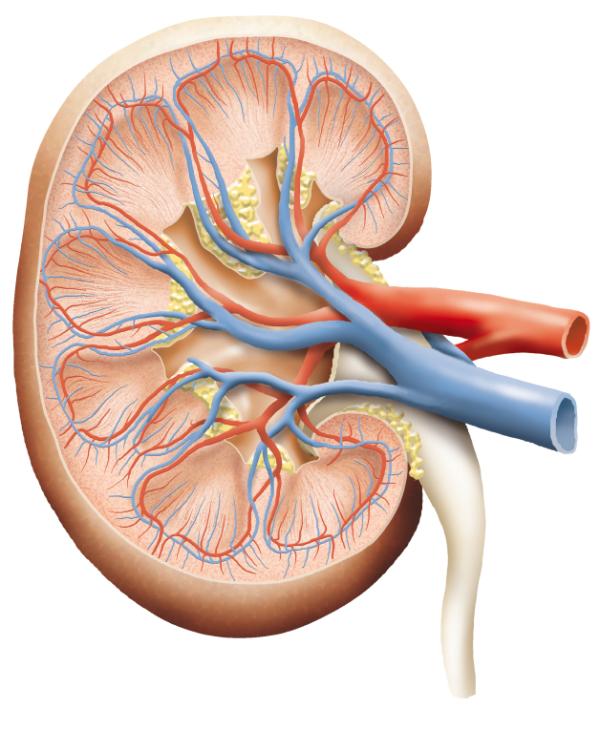

La creatinina es un compuesto que se libera en nuestro organismo a partir de la degradación de la creatina, un nutriente que fortalece nuestros músculos. Por lo tanto, la creatinina puede entenderse como un deshecho completamente natural, resultado del metabolismo de los músculos. Los riñones son los encargados de filtrarla y expulsarla del cuerpo a través de la orina.

- En la mayoría de ocasiones, una mala depuración de toxinas es debida a una insuficiencia renal, una afección por la cual los riñones no son capaces de eliminar los deshechos que se acumulan en la sangre como deberían. Un daño o infección en el riñón podría causar también esta condición.

- Otro motivo podría ser una obstrucción de las vías urinarias, un problema que impide el flujo de la orina hacia la uretra y que provoca un aumento de la presión en la zona, lo que puede derivar en afecciones mayores como cálculos renales, infecciones o un descenso de la función renal.